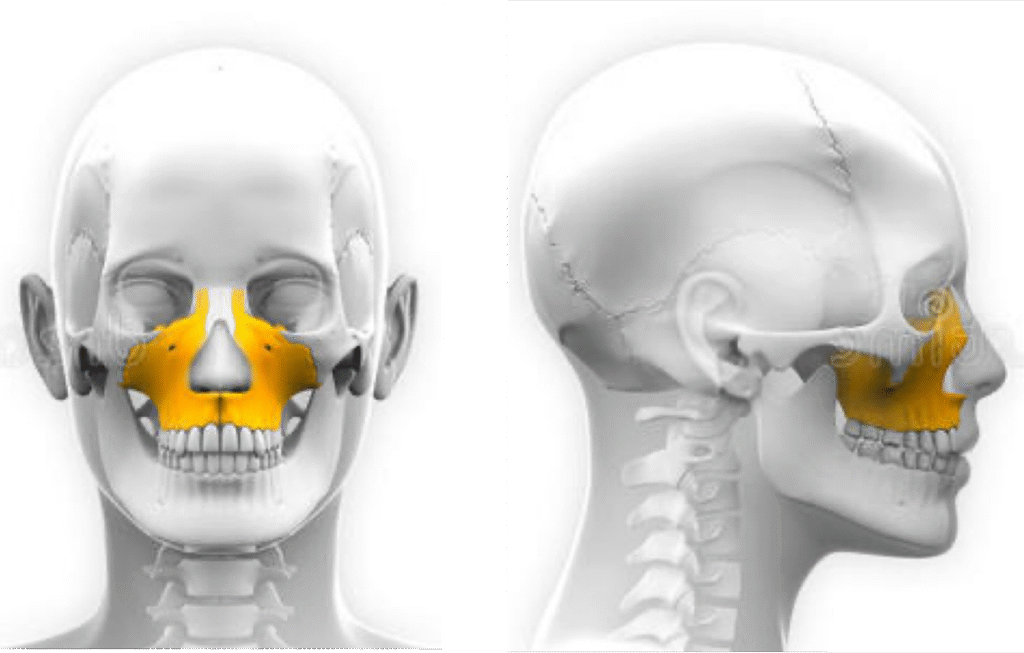

上顎骨由兩塊顎骨融合而成,骨縫在年紀增長後會關閉,屆時左右顎骨將融合成一整片上顎骨。 這道骨縫女性約在骨齡12歲左右會慢慢開始關閉,男性骨縫關閉的年齡約比女性晚1~2年(即骨齡13~14歲)。

上顎骨的擴張,可以實質藉由骨縫撐開增加寬度.下顎骨只有一塊骨頭,所以橫向擴張就只能是以牙齒移動帶動齒槽骨的方式。

如果上顎骨是天花板、也就是鼻腔的地板,所以其實是同一塊骨頭;當我把上顎骨”撐寬”的時候,鼻腔的管道也會跟著變寬,讓原本狹窄影響呼吸的鼻腔有所改善。